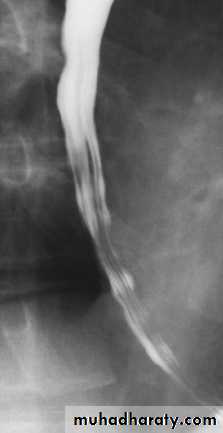

Achalasia

It is a neuromuscular abnormality result from failure of relaxation of the cardiac sphincter, which present at barium examination as a smooth , tapered narrowing always at the lower end of esophagus (bird beak or rat-tail appearance).There is associated dilatation of the esophagus, which often shows absent peristalsis. The dilated esophagus usually contains food residues and may be visible on CXR. The lungs may show consolidation and bronchiectasis from aspiration of the esophageal contents. The stomach gas bubble is usually absent.